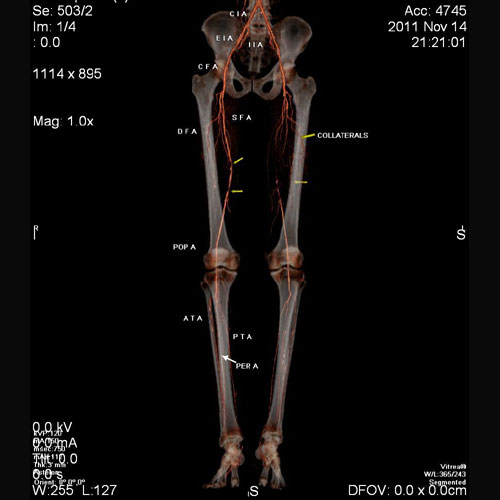

SCAN1

60 year old male with pain in left lower limb.

CT angiogram of both lower limbs shows diffuse atherosclerotic changes. Complete occlusion of proximal superficial femoral artery on left side with reformation of distal third at lower thigh through collaterals.